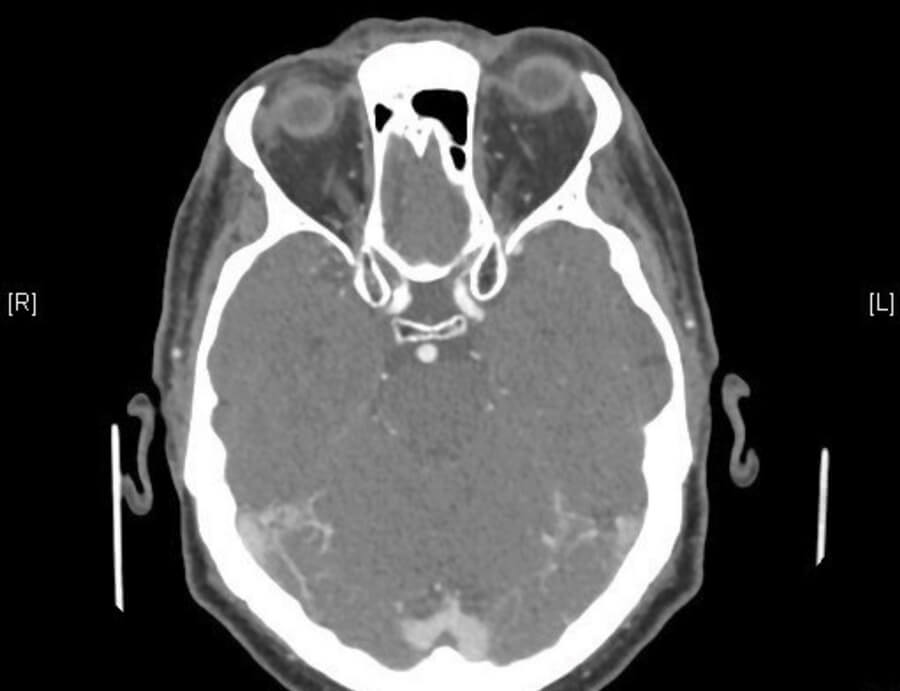

On ocular examination, his visual acuity was excellent at 6/6 in both eyes. Slit-lamp examination showed bilateral pseudophakia, with moderate left proptosis, lid and conjunctival chemosis, mildly raised intraocular pressure and a left VI nerve palsy (Figures 1 and 2). He had blood tests for full blood count (FBC), erythrocyte sedimentation rate (ESR), C-reactive protein (CRP) and thyroid function tests, as well as a brain and orbits CT scan plus angiogram (CTA) as the clinical signs were very localising to the left orbit / left cavernous sinus.

The CT / CTA findings confirmed the proptosis and enhancement of the left cavernous sinus as well as the left superior ophthalmic vein confirming the carotid - cavernous fistula (Figures 3 and 4).

Figure 3: Enhancement of left cavernous sinus on CTA (red arrow).